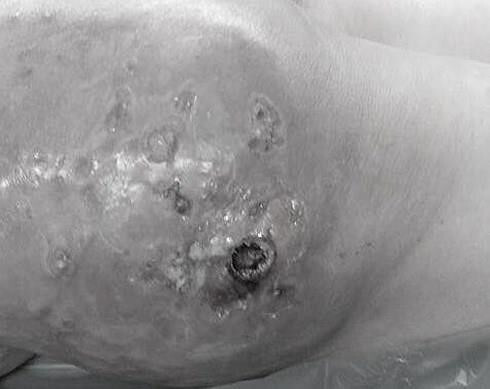

Bơm silicon để tạo tay búp măng, một người phụ nữ tại An Giang bị biến chứng gây áp xe sưng tấy phải nhập viện điều trị.